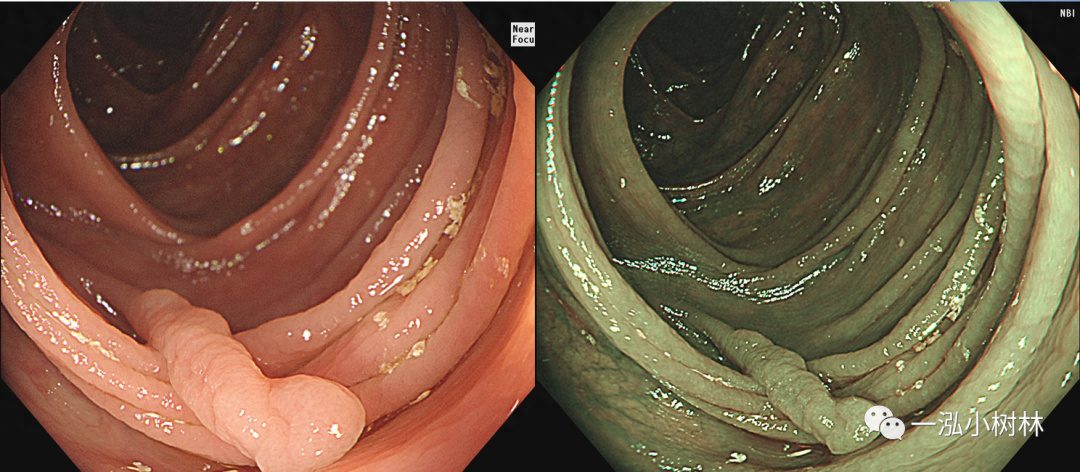

图13 结肠长蒂息肉